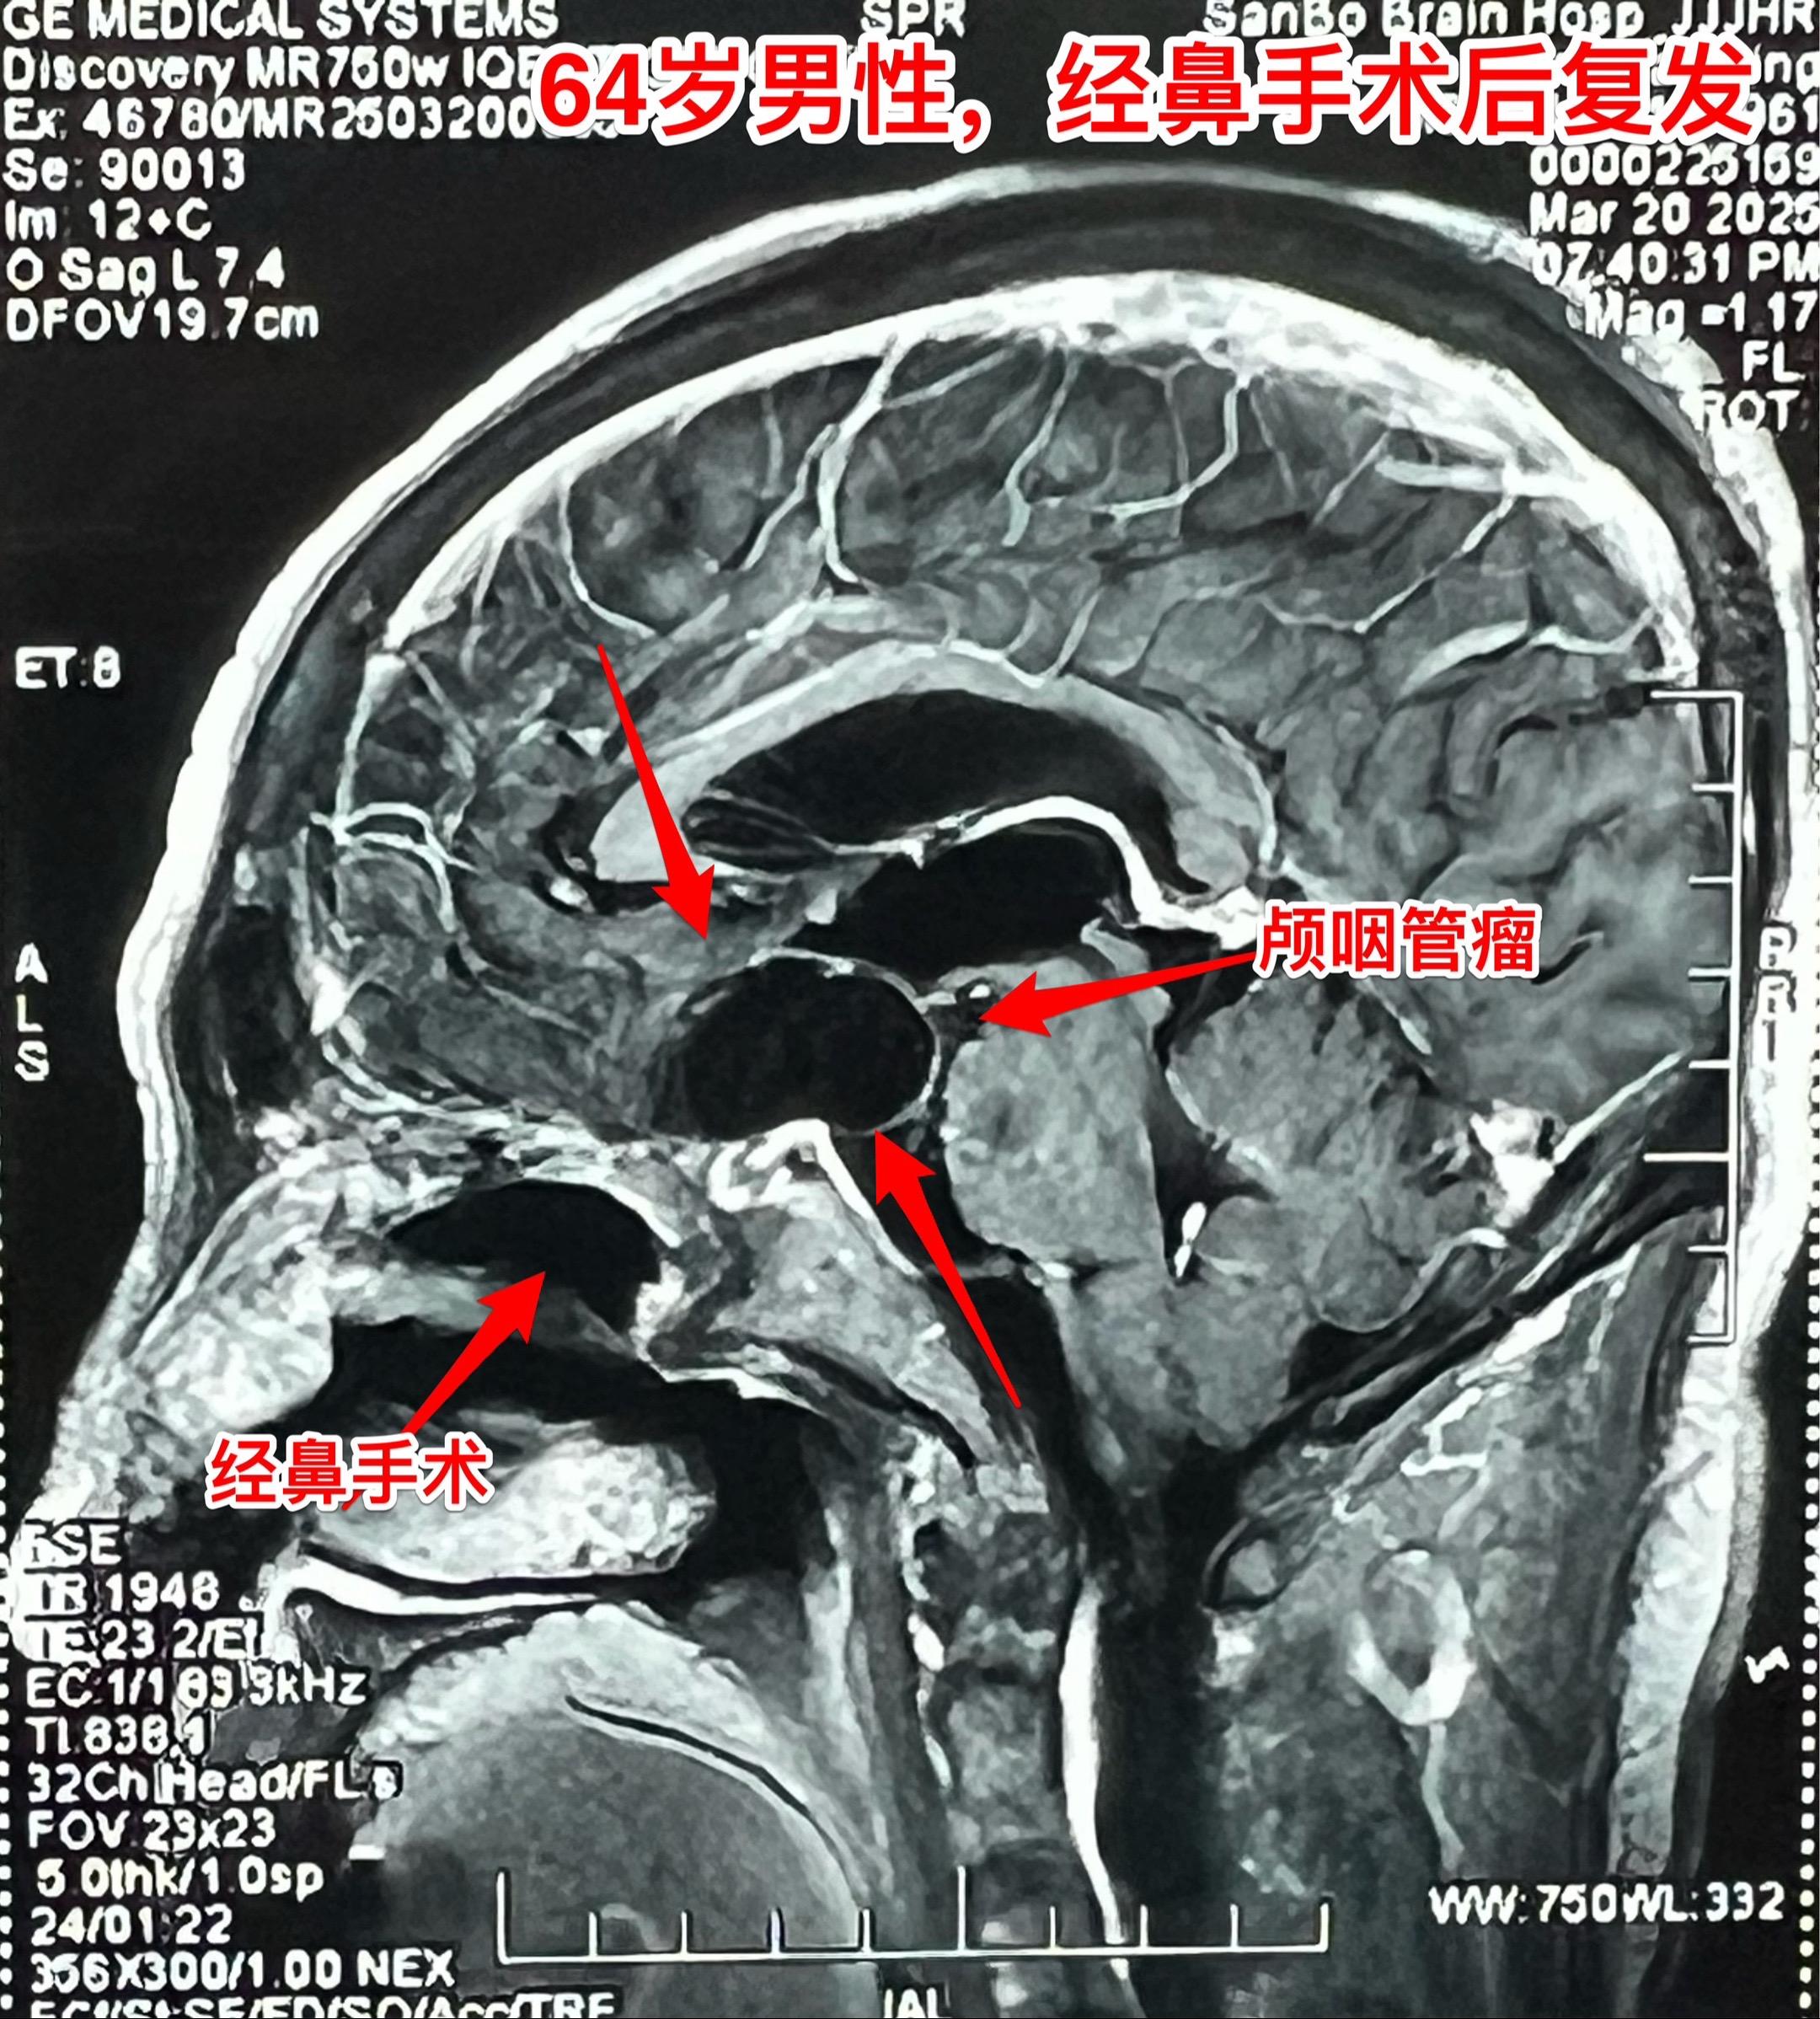

3月28日两个颅咽管瘤手术 两个都是经鼻手术手术后复发的颅咽管瘤手术。...

2025-03-20 08:19

今天的第二个颅咽管瘤手术。48岁女性,洛阳市人。因颅咽管瘤先后行经鼻手...

今天两个复发颅咽管瘤手术,顺利结束。展示的是今天的第二个病人,32岁...

昨天的第四个手术(经鼻复发颅咽管瘤)昨日第四个完成的手术,是38岁女性...